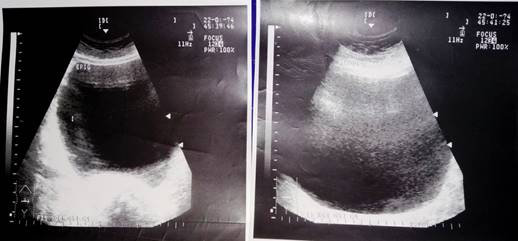

Estudios imagenológicos: se efectuaron tres USD de abdomen y siempre se señala quiste de ovario gigante o de grandes dimensiones que toma de hipogastrio a epigastrio, su diámetro fluctúo entre 17 a 23 cm con celularidad (Figura 3).

Resto de los estudios analíticos estuvieron entre límites normales excepto una leucocitosis muy discreta en dos exámenes con cifras respectivas de 9 500 y 10 300/mm3 y eritrosedimentación en 36 mm/h). En vista del dolor persistente y con tendencia a aumentar se decide el tratamiento quirúrgico urgente mediante laparotomía media baja ampliada. Se encontró un TQO derecho, gigante, necrosado, tenso y con adherencias; que se desgarra accidentalmente al manipularlo y se aspiran unos dos litros de contenido serohemático, se completa la ooforectomía total. Buena evolución en post operatorio. Biopsia: tumor quístico del ovario con marcados signos de necrosis por coagulación y hemorragia.